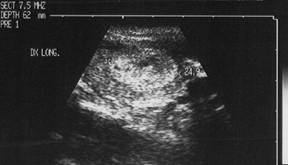

Recidiva linfonodale IN carcinom papilar

Barbat de 45 ani.

Recidiva linfonodala laterocervicala dreapta dupa tiroidectomie in urma cu trei

ani pentru carcinom papilar.